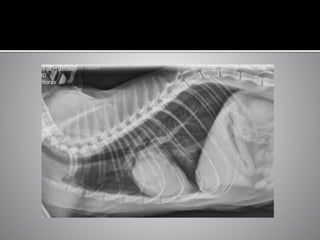

• #25 This was on the of the control dogs in the study Small breed dog, chronic cough While the heart looks big on radiographs, he only had mild LA enlargement on echo (LA:Ao 1.5) The reasons of the heart to look big are Shallow chest Expiratory film Both of these instances will result in a smaller volume chest on radiographs and, in relation, make the heart look bigger This dog was not in heart failure. He had a chronic cough and was treated with a combination of doxycyline/ theophylline and later oral/inhaled corticosteroids